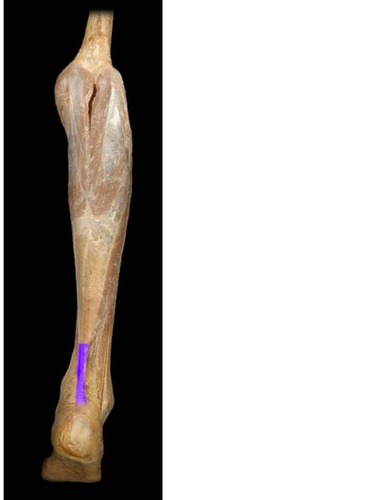

New cards

Tibial n.

knowt flashcard image

28

Common Fibula n.

Surface projection of tibial tuberosity

Surface projection of lateral malleolus